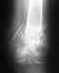

Разрушен позвонок.

Здравствуйте, уважаемые специалисты! Пациентка1939 г. р. , в мае 2013г была получена травма при падении с высоты. Диагностирован перелом позвонка. В августе сделан повторный рентген снимок, тревоги у травматолога он не вызвал. Был назначен массаж, после чего - "ничего", всё лечение. Неделю назад (январь 2014)появились острые боли в области рёбер, затем спины. После госпитализации в стационар рентген-снимки показывают разрушение позвонка, СОЭ завышено. С медициной у нас худенько (250 км от Екб.). Как можно провести диагностику, операцию, лечение на базе вашего института? Время очень ценно.Если можно контакты.Спасибо!